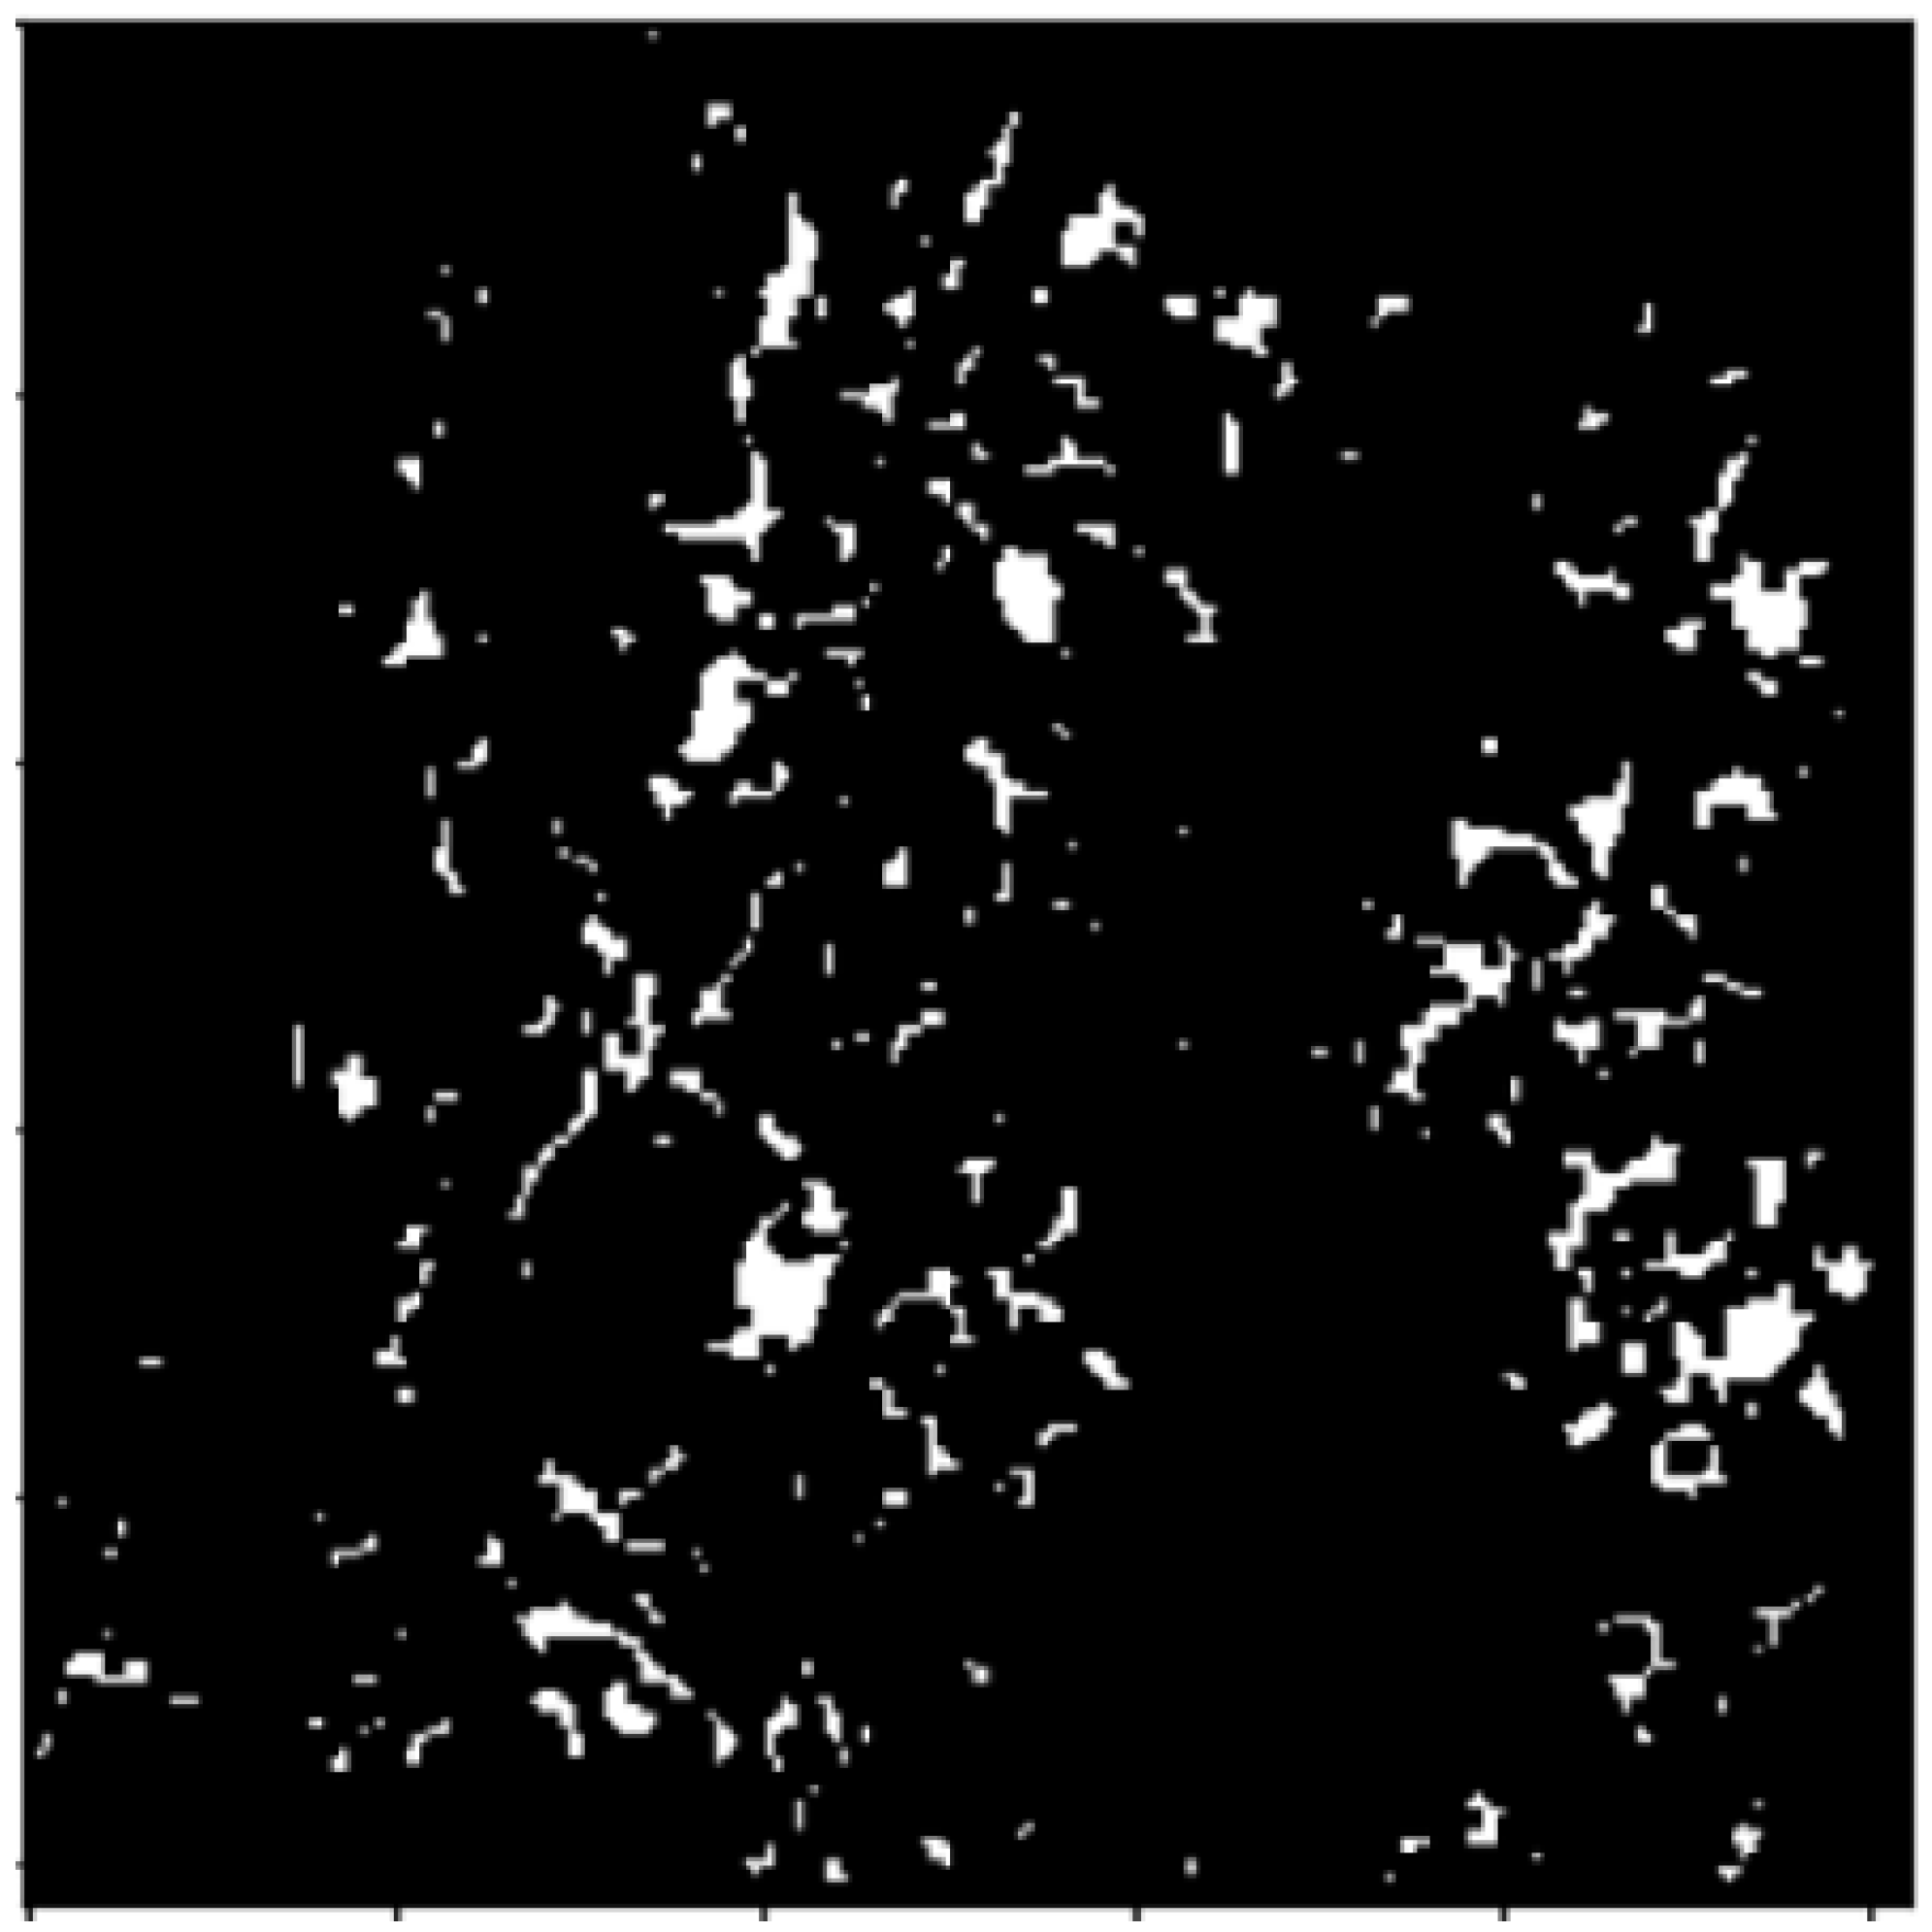

2.3.1. Connected Components

2.3.2. Watershed Segmentation